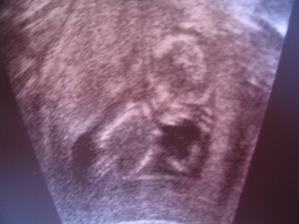

Letí to jak blázen, vždyť to znáš 🙂. Zatím nevíme nic, ale zítra jdeme na velký genetický UTZ, tak snad tam prcek nebude sedět v tureckém sedě jako minule 🙂))